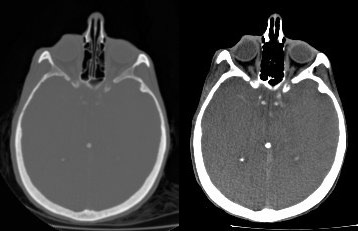

Ilustrácia k heslu kontrast

Snímka ľudskej hlavy vytvorená počítačovým tomografom. Kosť je svetlá, mäkké tkanivá sú sivé. Vľavo je neupravená snímka, vpravo kontrast upravený na skúmanie mäkkých tkanív.